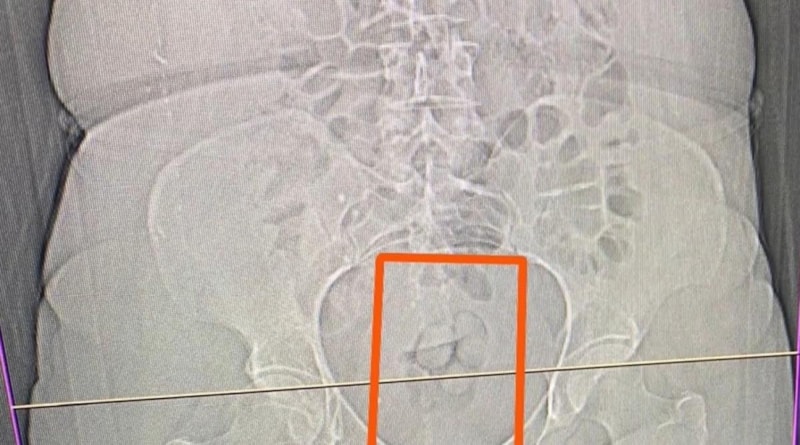

S.S. isimli şahsın şüpheli görülmesi üzerine çekilen tomografi neticesinde şahsın midesinde yabancı maddeler tespit edildi.

Yapılan iç beden muayenesi sonucunda ise şahıstan 21,39 gram metamfetamin maddesi ele geçirildi.